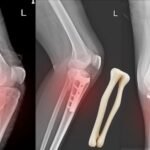

2. Fractures

When Bones break due to high-impact collisions, awkward falls, or overuse. Stress fractures in runners or traumatic fractures in contact sports, Fractures can occur in any sports injury.